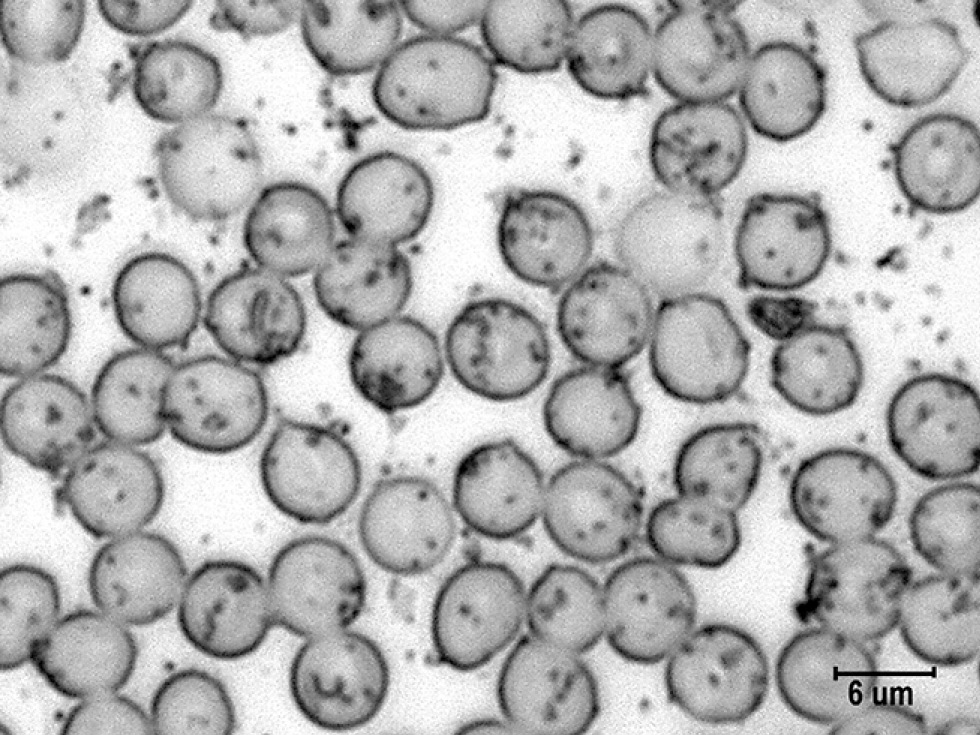

Согласно полученным данным (рис. 1), в мазках крови крыс в исходном состоянии эритроциты имели преимущественно округлую форму, иногда с неровными контурами, были окрашены равномерно, но в центральной зоне часто светлее, что обусловлено формой двояковогнутого диска. На поверхности эритроцитов были заметны тёмные гранулы в виде комочков или точек разных размеров. Это гранулы катехоламинов, выявленные путём импрегнации азотнокислым серебром [1].

Рис. 1. Гранулы катехоламинов на поверхности эритроцитов в мазках крови контрольных крыс. Импрегнация азотнокислым серебром с докраской эозином. Ув. ×4000. / Fig. 1. Granules of catecholamines on the surface of erythrocytes in the blood smears of control rats. Impregnation with silver nitrate and final staining with eosin. Magnification, ×4000.

Как видно на рис. 1 и табл. 2, на эритроцитах чаще встречались средние гранулы и несколько реже — мелкие и крупные гранулы катехоламинов. Количество мелких гранул составило 40±7,1 шт., средних — 72±16,1 шт., крупных 41±5,9 шт. Общее число гранул катехоламинов на поверхности 40 эритроцитов в контрольной серии равнялось 145–153 шт.